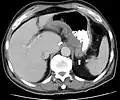

CT and MRI scans are useful for evaluating the small bowel with enteroclysis protocols.[160] They are also useful for looking for intra-abdominal complications of Crohn's disease, such as abscesses, small bowel obstructions, or fistulae.[161] Magnetic resonance imaging (MRI) is another option for imaging the small bowel as well as looking for complications, though it is more expensive and less readily available.[162] MRI techniques such as diffusion-weighted imaging and high-resolution imaging are more sensitive in detecting ulceration and inflammation compared to CT.[163][164]